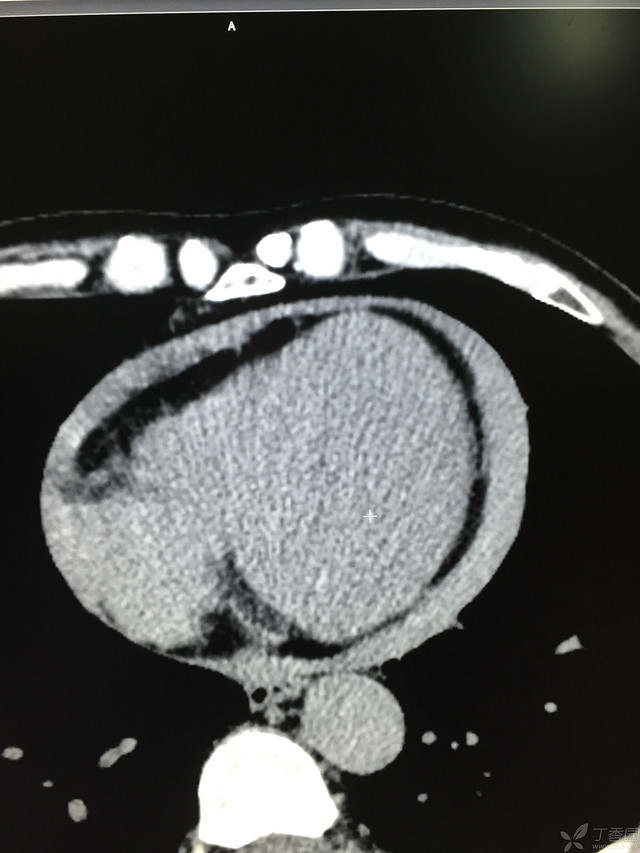

胸痛三天,加重三小时(CT是心包高密度影是什么)

患者性别:男

患者年龄:64岁

简要病史:三天前休息时突发胸前区疼痛伴大汗,到当地医院输液治疗后缓解,3小时前情绪激动后再次出现胸痛伴大汗,胸部压迫感,持续不缓解入院,到当地医院测血压180/?mmHg泵入硝酸甘油转入我院。

体格检查:血压94/72mmHg(右侧)96/74mmHg(左侧),心率78此/分,其他未见阳性体征